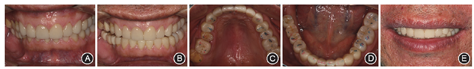

像

像;B:前伸

正面像;C:上颌

面像;D:下颌

面像;E:口唇部正面微笑像